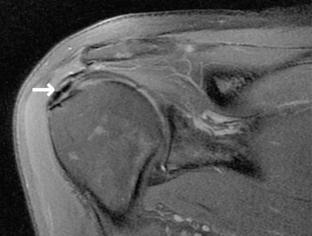

In this retrospective study, 30 patients were enrolled with a mean age of 44.8 ± 6.2years at surgery and a mean follow-up of 14.5 years (174 ± 24 months). Clinical evaluation was performed with the Simple Shoulder Test, Constant and Murley Score, the ASES Score and numeric analogue scales for pain, function and satisfaction. Additional postoperative MRI was performed in 20 of 30 patients to analyze the structural long-term results using the Sugaya classification. Long-term results were compared to the published mid-term (36 months) results as well.

22 female and eight male patients were included. The right shoulder was involved in 16 patients, in 14 patients the left shoulder was affected. The dominant side was treated in 17 patients. At follow-up examination, patients had a mean Constant score of 79.4 ± 1.9, a mean Simple Shoulder Test of 10.8 ± 1.9 points and a mean ASES Score of 88.1 ± 15.6 points. Numerical analogue scales showed a mean score of 1.37 ± 2.04 for pain, 8.57 ± 1.83 for function and 8.87 ± 2.32 for patient satisfaction. Compared to the mid-term results, the long-term results remained stable with no significant differences in the visual analog scales for pain function and patient satisfaction as well as the simple shoulder test (p < .05). Postoperative MRI examination at follow-up examination showed 14 Patients with type 1, four patients with type II and two patients with a type III according to the Sugaya Classification. No complete rotator cuff tears (type IV or type V) were seen.